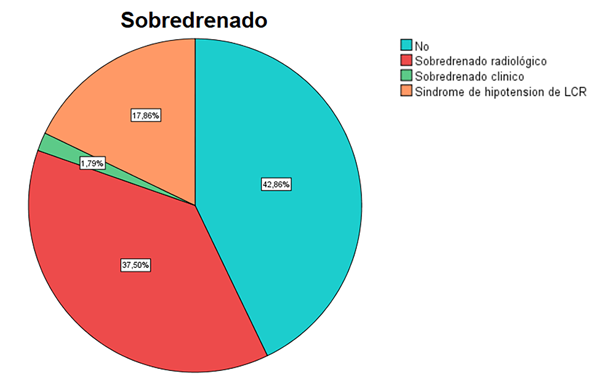

De la totalidad de la muestra, 32 pacientes (57%) presentaron sobredrenado (Fig. 2). El 37.4% se manifestó como sobredrenado radiológico puro, 1.8% como sobredrenado clínico puro y el 18% como síndrome de hipotensión de LCR constituido. Por otro lado, 10 pacientes (17.8%) presentaron higromas en imágenes postoperatorias, y de estos, 3 pacientes (5.4%) requirieron intervenciones quirúrgicas (dos ligaduras de VDVP y una evacuación de hematoma subdural). Otras complicaciones fueron la disfunción distal en un 5.4%, y meningitis e infección de sitio quirúrgico en un 3.6%. El follow-up medio fue de 27 meses (rango 6-90 meses).

Figura 2. Sobredrenado.

Del total de 56 pacientes, 32 pacientes (57%) presentaron sobredrenado. El 37.5% se manifestó como sobredrenado radiológico puro, 1.8% como sobredrenado clínico puro y el 18% como síndrome de hipotensión de LCR constituido (cambios imagenológicos asociados a clínica de hipotensión de líquido cefalorraquídeo).